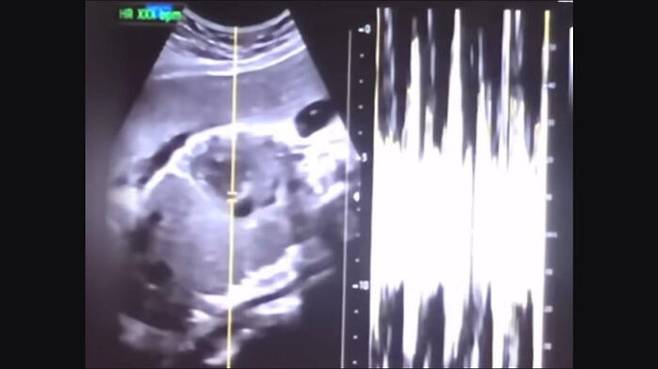

▲ 낙태한 산모의 유튜브 동영상에서 캡처한 초음파 사진과 심박 그래프